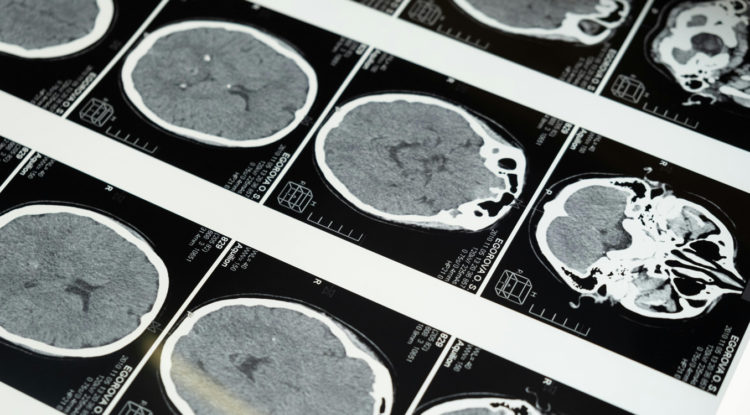

Фастфуд ухудшает работу мозга, а жить можно и без одного полушария?

Несмотря на то, что человеческий мозг начали изучать еще в древности, это все еще самый малоизученный орган нашего тела. Ученые до сих пор делают открытия о его работе, опровергая старые мифы — например, что мы используем лишь 10% его способностей или что нервные клетки не восстанавливаются. Проверьте, как много вы знаете о самом сложном органе своего тела в новом тесте «Холода».